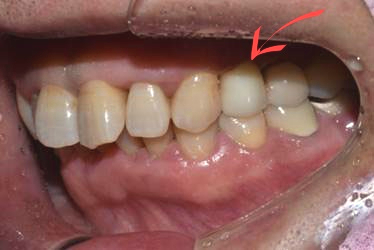

50대 남성분으로 본원에 오시기 2개월 전쯤 식사를 하시던 중 이가 깨지는 사고가 있었습니다.

곧바로 거주지 근처 치과에서 발치만 하시고, 임플란트 시술은 저희 디데이에서 진행하게 되셨는데요.

(전) 2021-09-29

사실 치아를 상실했을 때는 임플란트 시술을 빨리하는 것이 좋습니다.

치아가 없는 빈 공간으로 주변 치아가 옆으로 눕거나 이동하는 증상이 나타날 수 있기 때문입니다.

또한 위아래 치아가 서로 잘 맞물려야 하는데 이가 없다면, 남아있는 치아가 위로 올라가거나 아래로 내려앉는 증상이 생길 수 있어서 주의해야 합니다.

아울러 환자분은 치아가 없어 음식물이 계속 끼고, 말할 때 빈 공간이 보여 큰 불편감을 느끼셨는데요.

최종 보철물을 올리기 전에는 임시치아를 해드리기 때문에 큰 불편감 없이 지내실 수 있습니다.

앞서 말씀드린 SCRP 방식으로 치료를 마친 모습입니다.

(후) 2022-01-18